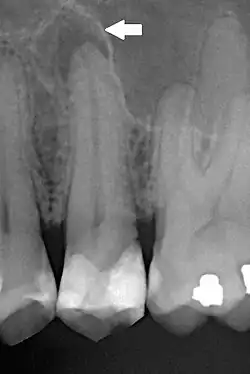

Periapical dental radiograph showing chronic periapical periodontitis on the root of the left maxillary second premolar. Note large restoration present in the tooth, which will have undergone pulpal necrosis at some point before the development of this lesion. | |